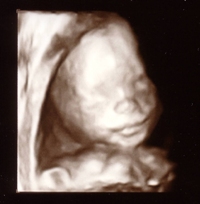

sunflowerjesss

Mommy to 3!

Member since 10/05 20369 total posts

Name: Jesss, duh.

Re: Sono pics... can i see your 20 week ones?

Mine s u c k too!

We don't have any profile shots because would not turn his head. So I am going back next friday.

But, here are the pics we got:

I highlighted what I *think* is his penis, but I could be wrong. I know the pee pee is in that sono pic, just couldn't figure out where :lol"